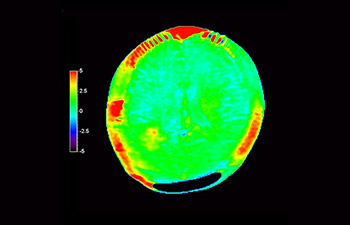

Chemical exchange saturation transfer(CEST)imagingは、MRIにおける分子イメージングの手法であり、その代表的なものにamide protontransfer(APT)imagingがある。MRIはプロトン密度と緩和時間に基づいた画像コントラストを得るのに対し、APT imagingでは可動性タンパク中のペプチド(アミド基)の濃度と交換速度に基づくコントラストが得られ、脳腫瘍の悪性度判定や放射線壊死と脳腫瘍再発との鑑別などに応用されている¹,²。

APTwイメージングでは、アミド基(NH)が対象となる。生体内のアミド基は、主にタンパク質やペプチドに含まれており、平均的には +3.5ppmの周波数に分布するとされる。アミド基のプロトンはバルク水から +3.5ppm離れた周波数帯に存在するため、交換プロトンの信号を抑制させる飽和パルスを +3.5ppmで選択的に照射する。飽和パルスによって信号が抑制されたアミド基のプロトンは、バルク水へ順次移動し、バルク水の信号を低下させる。飽和パルスの周波数を変化させながらバルク水の信号抑制を観察することで、間接的にアミド基を観察することができる(図1)。

CESTは、ごくわずかな共鳴周波数差(数100Hz)にあるプロトンを選択的に飽和させて画像化するため、静磁場B0(数十MHz)のわずかなズレでも、結果に大きな誤差が生じる。APTwイメージングでは、3D DIXON TSEシーケンスを用いB0補正を行っている。本シークエンスの利点は、3 point Dixonによる高精度のB0補正と撮像を一体化させB0不均一性に強い点と、スライスギャップなく3Dで広範囲の撮像が可能となった点である。これにより、B0不均一性に強く安定して広範囲のAPT強調像を撮像することができる⁴。